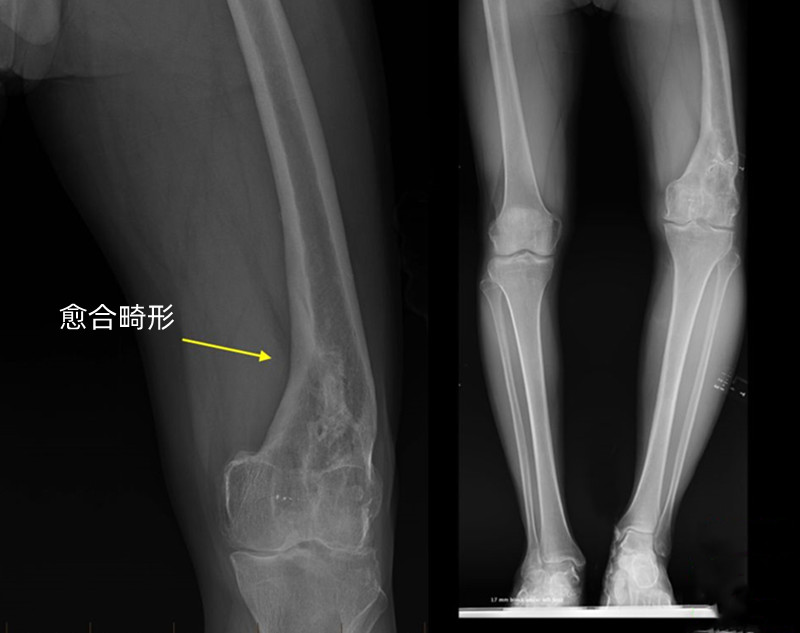

骨折后通常都要进行复位。如果复位或固定不良等其他原因,骨折的断端没有对齐,骨头愈合后不直了,形成了一个角度或者发生了重叠或者旋转,造成一条腿长一条腿短。原因和骨折复位不佳,固定不牢固,过早地拆除固定,还有就是复位的太晚了,骨折已经开始了错误的愈合。

不注意这些迹象的话,康复后可能出现腿长不一致,走路跛行,或者 脚内旋或外旋,还可能引起臀部,膝盖和脚踝的问题,这是由于畸形愈合打破了下肢的正常力线,其他关节被迫承受过大的压力。

如果出现了畸形愈合,也不一定对以后造成严重影响,每个人的腿长差异本来就不同,只要相差不超过2厘米,基本上不会太影响下肢功能,也不会带来其他关节的疼痛和不适,还有些十几岁的孩子,畸形不严重的情况下也有可能随着生长自行矫正。总之要根据具体情况决定是否需要再次进行手术矫正,畸形矫正手术通常针对以下症状: